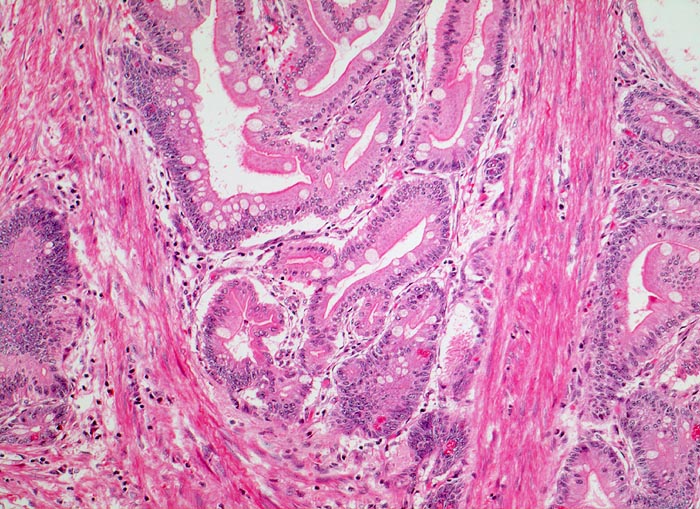

PathoPic ID 3059 - Peutz Jegher Polyp

Peutz Jegher Polyp

benigner Tumor

Jejunum

Darm, Anus

Zwischen den enterisch differenzierten Epithelverbänden mit Lamina propria verlaufen breite Stränge glatter Muskulatur.

Breitbasiger Polyp von 3cm Durchmesser.

Eisenmangelanämie und wiederholte Abdominalschmerzen infolge von Intussusception.

Epithelverlagerungen in die Submukosa und Muscularis propria kommen nur in Dünndarmpolypen vor.

Histologie

100

7